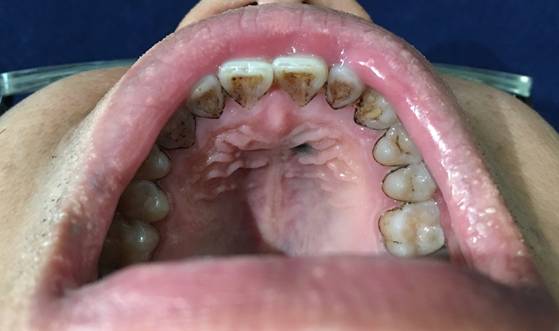

食物:民以食为天,我们每天都要通过口腔摄入大量的食物,而几乎每种食物都含有色素,其中包括咖啡、果汁、巧克力等富含色素又容易在口腔残留的食物,这些食物在咀嚼过程中很容易在口腔各个区域沉积,如果没有及时清理出去,久而久之就会导致口腔黏膜发黑。色素同时也会在牙齿上沉积,导致周围牙齿发黑(图1)。

图1:食物导致口腔腭部黏膜发黑,同时伴有很多牙齿发黑。